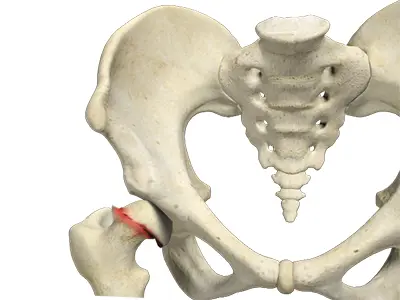

SCFE is a condition seen in preadolescents and adolescents where the femoral head (ball of the hip) slips out of alignment due to damage or weakness of the growth plate. This misalignment can disrupt blood flow to the hip and lead to pain and long-term joint problems. SCFE is more commonly seen in males between ages 10 and 15 and usually occurs without trauma or sports injury.

SCFE can be confused with other pediatric hip conditions such as: - Legg-Calve-Perthes Disease